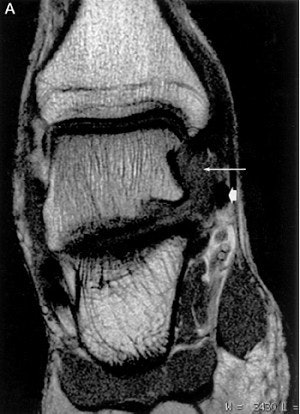

Coronal (A) and sagittal (B) MR images of PTTL injury

(arrow) with marked scar formation and hypertrophic response. The medial collateral ligament is lifted off the bone strictures of the medial ankle gutter by the volume scar formation. Encasement of the tibialis posterior tendon is noted (arrowhead). These findings are confirmed on ultrasound (C), which also detects the presence of calcific densities in the ankle gutter, either as a result of avulsion or dystrophic calcification.